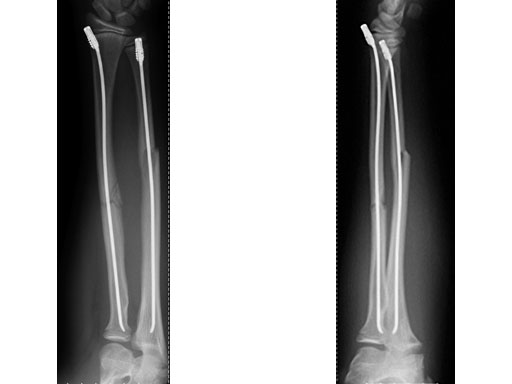

Case 2: Oblique forearm, shaft fracture (22D/5.1) with end caps, 11-year-old boy.

Case provided by Theddy Slongo, Bern, Switzerland